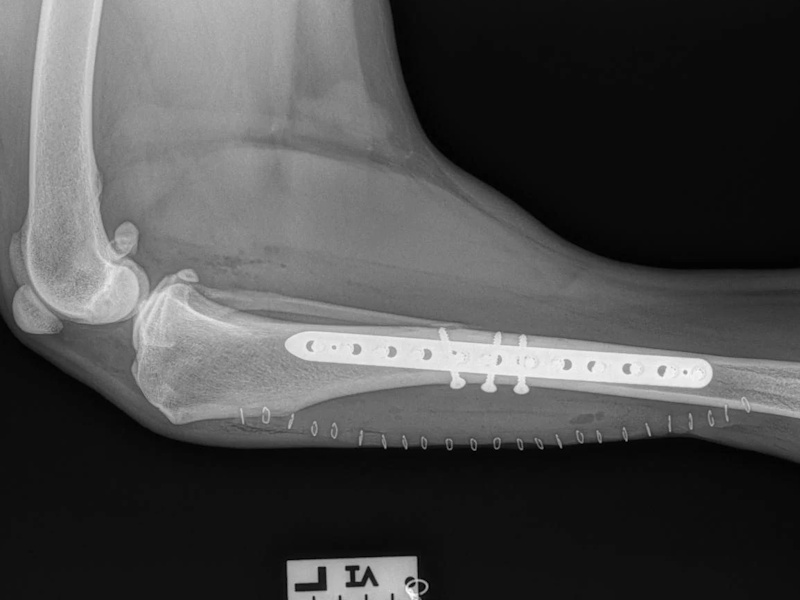

Tibial Plateau Leveling Osteotomy (TPLO) - additional information

An osteotomy is a surgical cut in a bone. In the cruciate deficient stifle, a cut is made in the top of the tibia. The top portion of bone that contains the articular surface is rotated to level it. The two pieces of bone are held in place with a metal plate and screws.

Post Surgical Radiographs

While the patient is still anesthetized, the patient is taken into radiology for post-surgery radiographs (X-rays). The radiographs are assessed to measure the new tibial plateau angle. We are aiming for 5-6 degrees relative to the long axis of the tibia. The apparatus (plate and screws) are assessed for size and appropriate position.